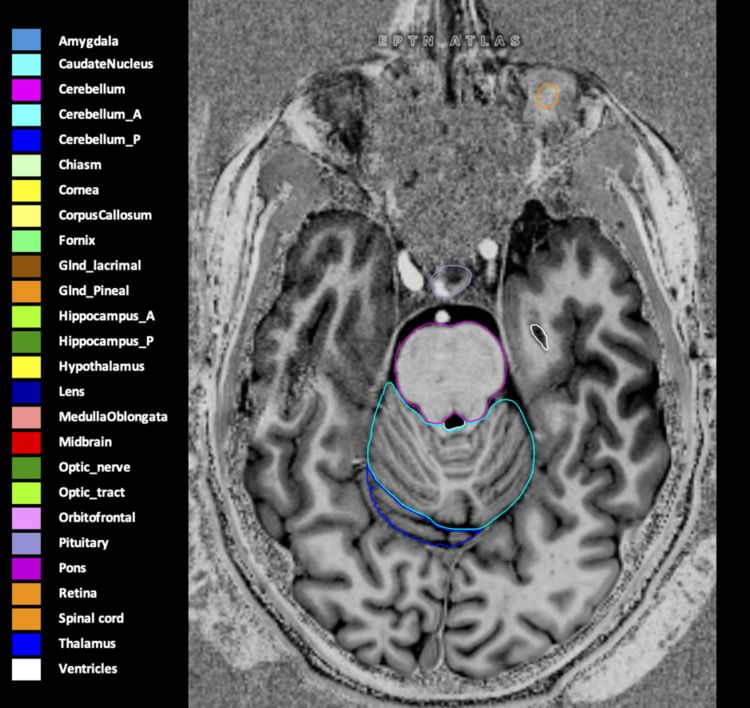

Eekers et al. have published an international neurological atlas for contouring of organs at risk in consensus with the European Particle Therapy Network (EPTN) in 2018 and an update in 2021. The purpose of this consensus atlas is to decrease inter- and intra-observer variability in delineating OARs relevant for neuro-oncology.

Included are all OARs known to be relevant for radiation-induced toxicity in neuro-oncology: brain, brainstem (midbrain, pons, medulla oblongata), chiasm, cerebellum (anterior & posterior), cochlea, cornea, hippocampus (anterior & posterior), hypothalamus, lens, lacrimal gland, optic nerve, pituitary, skin, and vestibular & semicircular canals. To further facilitate research on cognition, vision and radiological changes after irradiation of the brain, potential clinically-relevant OARs are included: amygdala, caudate nucleus, cerebellum (anterior & posterior), corpus callosum, fornix, macula, optic tract, orbitofrontal cortex, periventricular space (PVS), pineal gland, and thalamus.

Three-dimensional delineation of the 25 consensus OARs for neuro-oncology are shown on CT (WW/WL 120/40, 3000/600), 3T MR images, (T1Gd, T2FLAIR 1mm) and 7T MR (MP2RAGE 0.7 mm). All are presented in transversal, sagittal and coronal view.